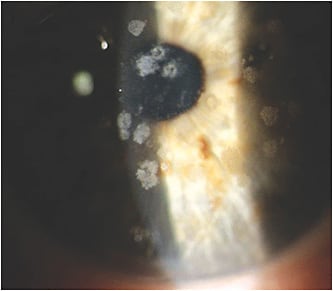

Granular Corneal Dystrophy (GCD)

The granular corneal dystrophy name comes from the appearance of small particles that are reminiscent of breadcrumbs. They may be viewed with a thin optic section or sclerotic scatter.4 Anterior segment OCT can be helpful in locating and quantifying the lesions. Initially, the corneal surface may be uniform and smooth; however, as the condition progresses, the corneal surface may become more irregular. Although confined to the anterior stroma, epithelial integrity and function may be affected. As the dystrophy progresses, patients may become photophobic. Recurrent corneal erosions (RCEs) may occur, requiring appropriate management.5